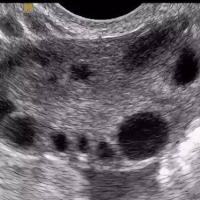

| АМГ вырабатывают фолликулы – маленькие пузырьки в яичниках, внутри которых «живут» незрелые яйцеклетки. | ![]() |

Так как АМГ вырабатывают фолликулы, его концентрация напрямую отражает их количество и активность:

![]() много фолликулов - высокий АМГ |

![]() мало фолликулов - низкий АМГ |